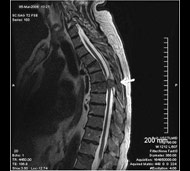

Спинальна магнітно-резонансна томографія (МРТ). Замість радіаційного випромінювання в МРТ використовуються потужні магнітні і радіохвилі для отримання зображення поперечного перерізу хребта. МРТ чітко відображає спинний мозок і нерви і забезпечує краще зображення пухлин кісток, ніж комп'ютерна томографія (КТ). Вам можуть ввести в вену кисті або передпліччя контрастну речовину, яка висвітлює деякі пухлини. Крім цього, використовують сканери з високою інтенсивністю сигналу для виявлення невеликих пухлин, які можна не помітити.

Інтрамедулярні пухлини. Ці пухлини беруть початок всередині спинного мозку. Більшість з них є астроцитоми, частіше за все вони розвиваються у дітей та підлітків, або епендимоми, найпоширеніший тип пухлин спинного мозку у дорослих. Часто інтрамедулярні пухлини є судинними гемангіобластомами спинного мозку. Інтрамедулярні пухлини можуть бути або доброякісними, або злоякісними і, залежно від їх розташування, вони можуть викликати оніміння, втрату чутливості або зміни в роботі кишечника або сечового міхура. У рідкісних випадках пухлини з інших частин тіла можуть метастазувати в спинний мозок.